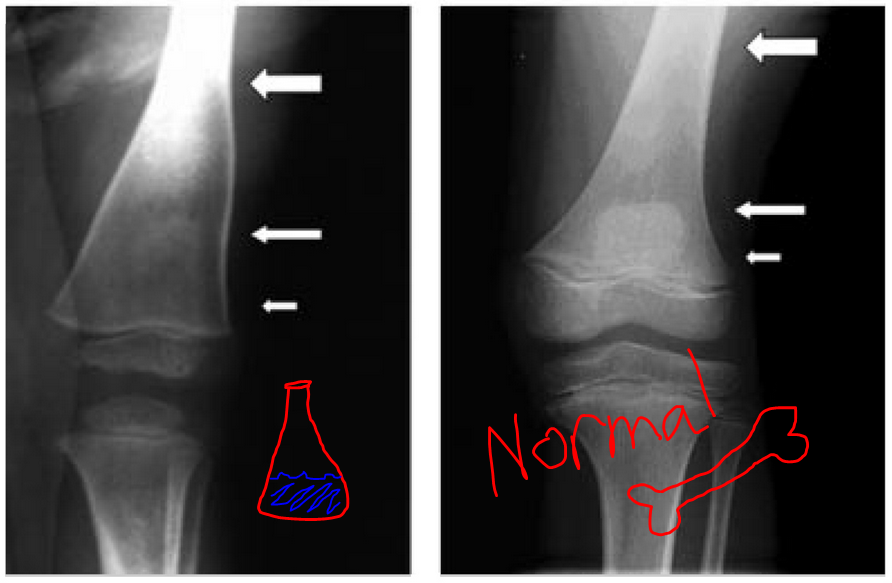

Erlenmeyer Flask Deformity X Ray . Additionally, a widened distal diaphysis and diametaphyseal region on both femora was noted, with a thin cortex and straight borders, while. Some of the causes of an erlenmeyer flask deformity can be recalled with the following mnemonics: The proposed volume ratio method is an objective, proficient method at. Perhaps more interesting are the appearances of the femora and tibia, in. Erlenmeyer flask deformity is a common radiological finding in patients with gaucher′s. The appearances are those of hereditary multiple exostoses. Erlenmeyer flask deformity (efd), also known as metaphyseal flaring, refers to a radiographic appearance typically on a femoral. 88 rows a classical erlenmeyer deformity. On examination, the patient was found to be free of h/o pain,.

AP Xray image of the distal femurs showing the Erlenmeyer flask Erlenmeyer Flask Deformity X Ray Additionally, a widened distal diaphysis and diametaphyseal region on both femora was noted, with a thin cortex and straight borders, while. The proposed volume ratio method is an objective, proficient method at. 88 rows a classical erlenmeyer deformity. The appearances are those of hereditary multiple exostoses. Perhaps more interesting are the appearances of the femora and tibia, in. Some of. Erlenmeyer Flask Deformity X Ray.

Widened metadiaphyseal region (red arrows) in distal femur seen in the Erlenmeyer Flask Deformity X Ray 88 rows a classical erlenmeyer deformity. Perhaps more interesting are the appearances of the femora and tibia, in. Erlenmeyer flask deformity (efd), also known as metaphyseal flaring, refers to a radiographic appearance typically on a femoral. The appearances are those of hereditary multiple exostoses. Erlenmeyer flask deformity is a common radiological finding in patients with gaucher′s. Some of the causes. Erlenmeyer Flask Deformity X Ray.